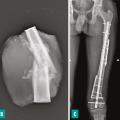

Prise en charge chirurgicale des sarcomes osseux

La résection d’un sarcome osseux a pour objectif d’obtenir des marges adaptées, en privilégiant les chirurgies conservatrices, tout en s’efforçant de préserver la meilleure qualité de vie.1 La chirurgie doit être effectuée par une équipe spécialisée dans un centre de référence intégré au réseau NetSarc+, ce qui diminue le risque de…